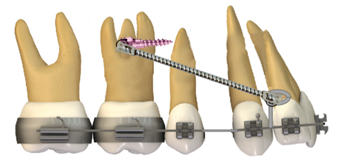

Camuflaje con extracción de primeros premolares superiores y minitornillos interradiculares.

En esta técnica inicialmente se deben realizar las extracciones de los primeros premolares superiores junto con la inserción de minitornillo en la misma cita, el mismo debe ser de tipo autoperforante (1,4 mm de diámetro y 8 mm de longitud) colocándolo entre las raíces del primer molar superior y el segundo premolar de forma bilateral. Los minitornillos se cargan inmediatamente con una cadena elastomérica para la retracción del canino hacia una Clase I, posterior a esto se coloca resortes helicoidales cerrados de níquel-titanio (NiTi) que van desde un bucle elaborado en el arco de acero 0.017x0.025 pulgadas o desde un hook crimpable en el arco del mismo calibre (figura 2 y 3), con una fuerza de 150 gr con el vector de fuerza pasando por arriba del centro de resistencia de tal manera que los dientes antero superiores se retraigan de manera simultánea hacia arriba y atrás, las fuerzas aplicadas se repiten cada veintiún días permitiendo el cierre de espacio de las extracciones 14.

Figura 2. Cierre de espacio de las extracciones.

Elaboración: Los autores.